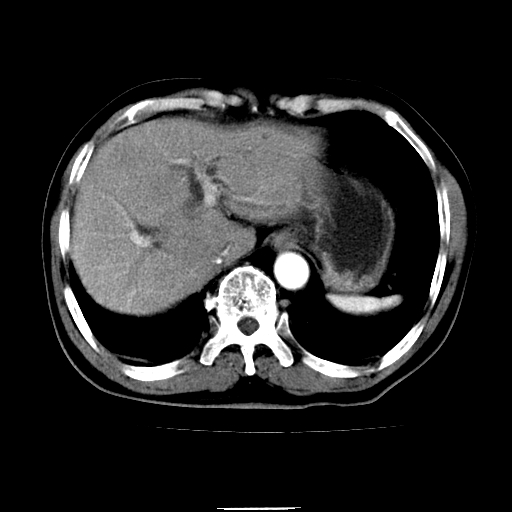

以下是引用chenqiong在2010-3-25 20:56:00的发言:[br]1、胆囊炎,胆囊息肉[br]2、肝内胆管及胆总管扩张,胆总管下端结石[br]3、十二指肠乳头旁憩室

以下是引用zxl51642在2010-3-26 10:47:00的发言:[br]胆囊炎,胆囊息肉,胆总管扩张,但未看到明显肿块,肝内胆管扩张不像恶性,炎性狭窄或阴性结石可能吧,建议mrcp,右肾小囊肿